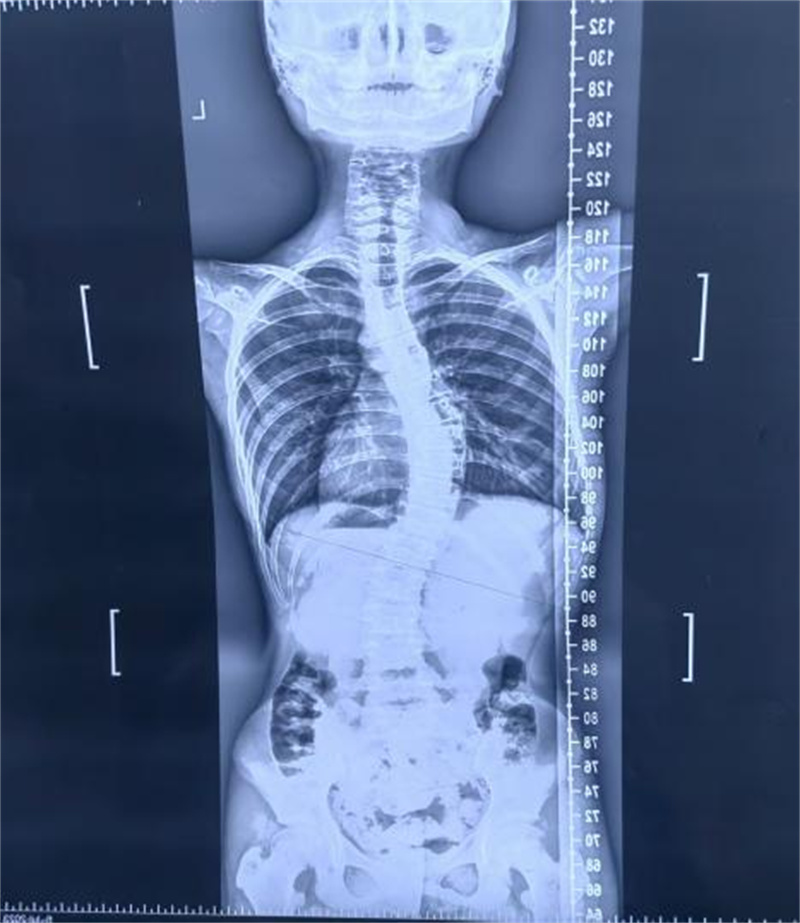

一.复查x片

2.预防并发症:严重的脊柱侧弯患者会因为腰背部肌肉不对称导致腰背部出现疼痛,而且脊柱侧弯会导致胸廓畸形,胸廓里面的心肺及腰腹部的肠胃因此受到挤压,最终导致心肺功能和胃肠功能受损,及时进行复查可以早期发现这些并发症。